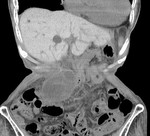

[画像診断]胆嚢捻転症、CT所見について 2011-04-12